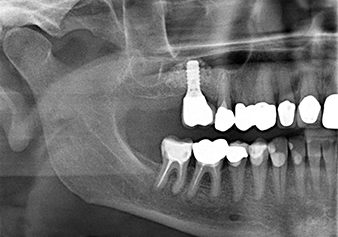

A 49-year-old female patient, a non-smoker and with nothing remarkable in her general medical history, was referred to our oral surgery practice for surgical extraction of tooth 16 and subsequent implantation. After the extraction, the patient experienced mild sinusitis trouble with the resultthat we initially waited six months before carrying out the measure. The residual bone height at the planned implant position measured 3-4 mm (Fig. 1 and 2).

Implantation and prosthetic restoration

To move the augmentation material in the direction of the maxillary sinus atraumatically, the implant was inserted very slowly by hand (Fig. 9). In the process, the membrane was pushed in the cranial direction once again. After two months, the surgical site healed without irritation. Six months later, the x-ray check showed a significant increase in opacity as an indication of ossification (Fig. 10). The prosthetic restoration was carried out with a metal-ceramic crown.